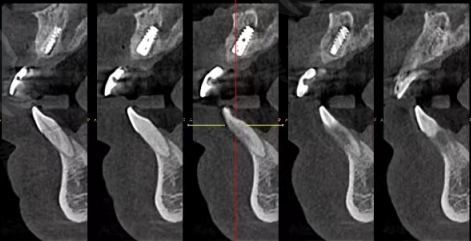

- CBCT三维成像:种牙前一必备,毫米级计算神经血管位置

- 数字导板种植+微创植入:更快捷修复快,术后少肿